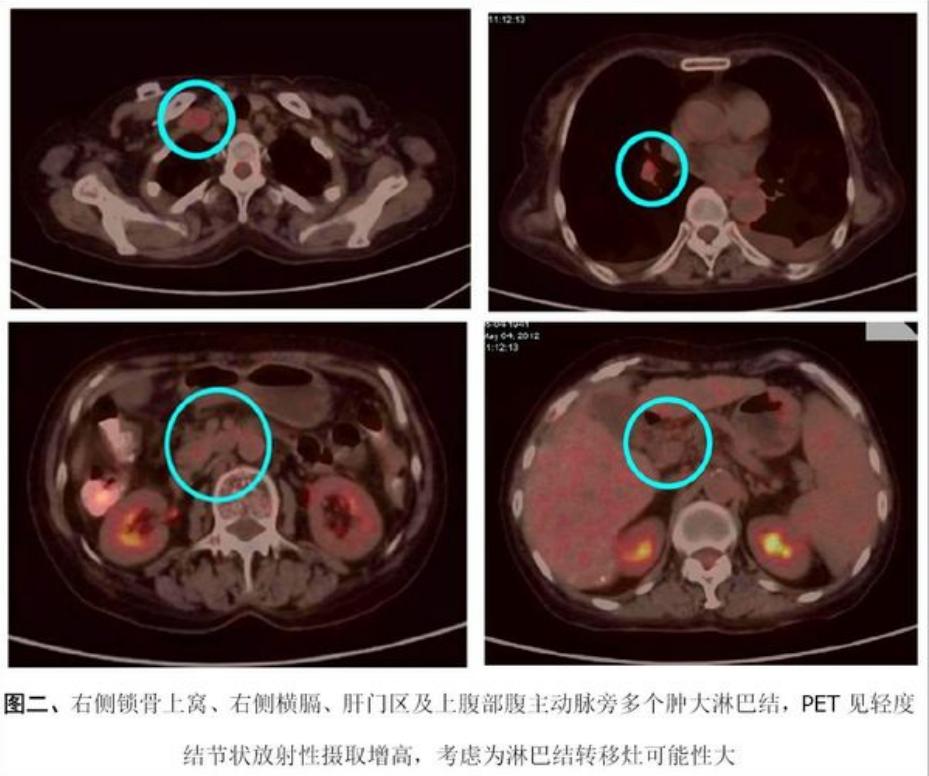

2012-5-4行PET/CT检查,结果如下:

2012年4月,陈女士发现在右侧锁骨上出现一个包块并迅速增大,甲胎蛋白达到2700ng/ml,考虑肿瘤复发并转移。2012年5月开始服用靶向药物多吉美治疗,但因不耐受药物副作用,没用多久就停用了。